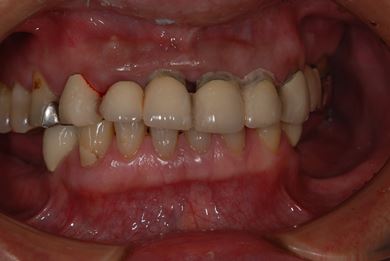

インプラントの症例写真 IMPLANT

骨再生スピードインプラント治療+セラミック治療

| 性別/年齢 | 男性 / 53歳 | ||||||||||||||||||||||||||||||||

| 主訴 | インプラント治療の相談。 | ||||||||||||||||||||||||||||||||

| 治療方針 | 上前歯部は、抜歯と同時にインプラントを埋入し、治療期間を短縮する。左上奥は、ソケットリフトにて上顎洞を拳上し、インプラント治療を可能にする。 | ||||||||||||||||||||||||||||||||

| 治療内容 | インプラント4本(ソケットリフト・抜歯即日)、テンポラリーインプラント2本、メタルボンドクラウン9本 | ||||||||||||||||||||||||||||||||

| 総治療費 | 2,025,975円 | ||||||||||||||||||||||||||||||||

| 治療期間 | 1年9ヶ月 |